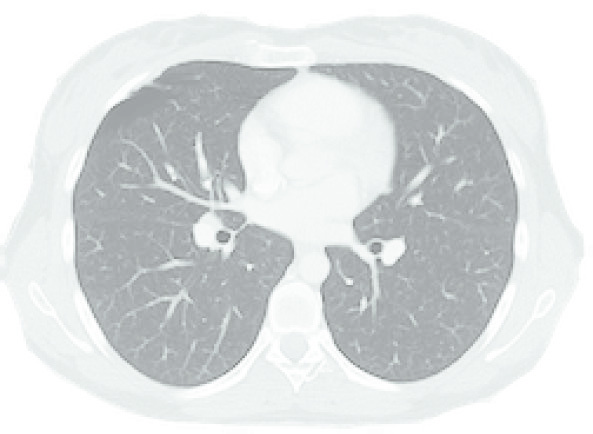

A diferença entre algoritmos se manifesta mais claramente em condições desafiadoras: campos pequenos, feixes de alta energia e heterogeneidades acentuadas — especialmente pulmão. A figura ao lado ilustra isso de forma dramática: para um feixe de 15 MV, campo 2,8×14 cm, 4 cm off-axis, atravessando 10 cm de pulmão (ρ = 0,2 g/cm³), as curvas de dose em profundidade divergem significativamente entre os algoritmos.

Monte Carlo ($MC_w$) serve como referência. O Collapsed Cone (CC-TMS, CC-PIN) acompanha razoavelmente bem, com desvios moderados na interface e dentro do pulmão. O AAA (AAA-ECL) segue de perto o CCC mas com desvios na interface tecido-pulmão. Já o Pencil Beam (PB-TMS, PBC-ECL) superestima a dose dentro do pulmão por uma margem clinicamente significativa e não consegue reproduzir a redução de dose lateral causada pela falta de equilíbrio eletrônico.